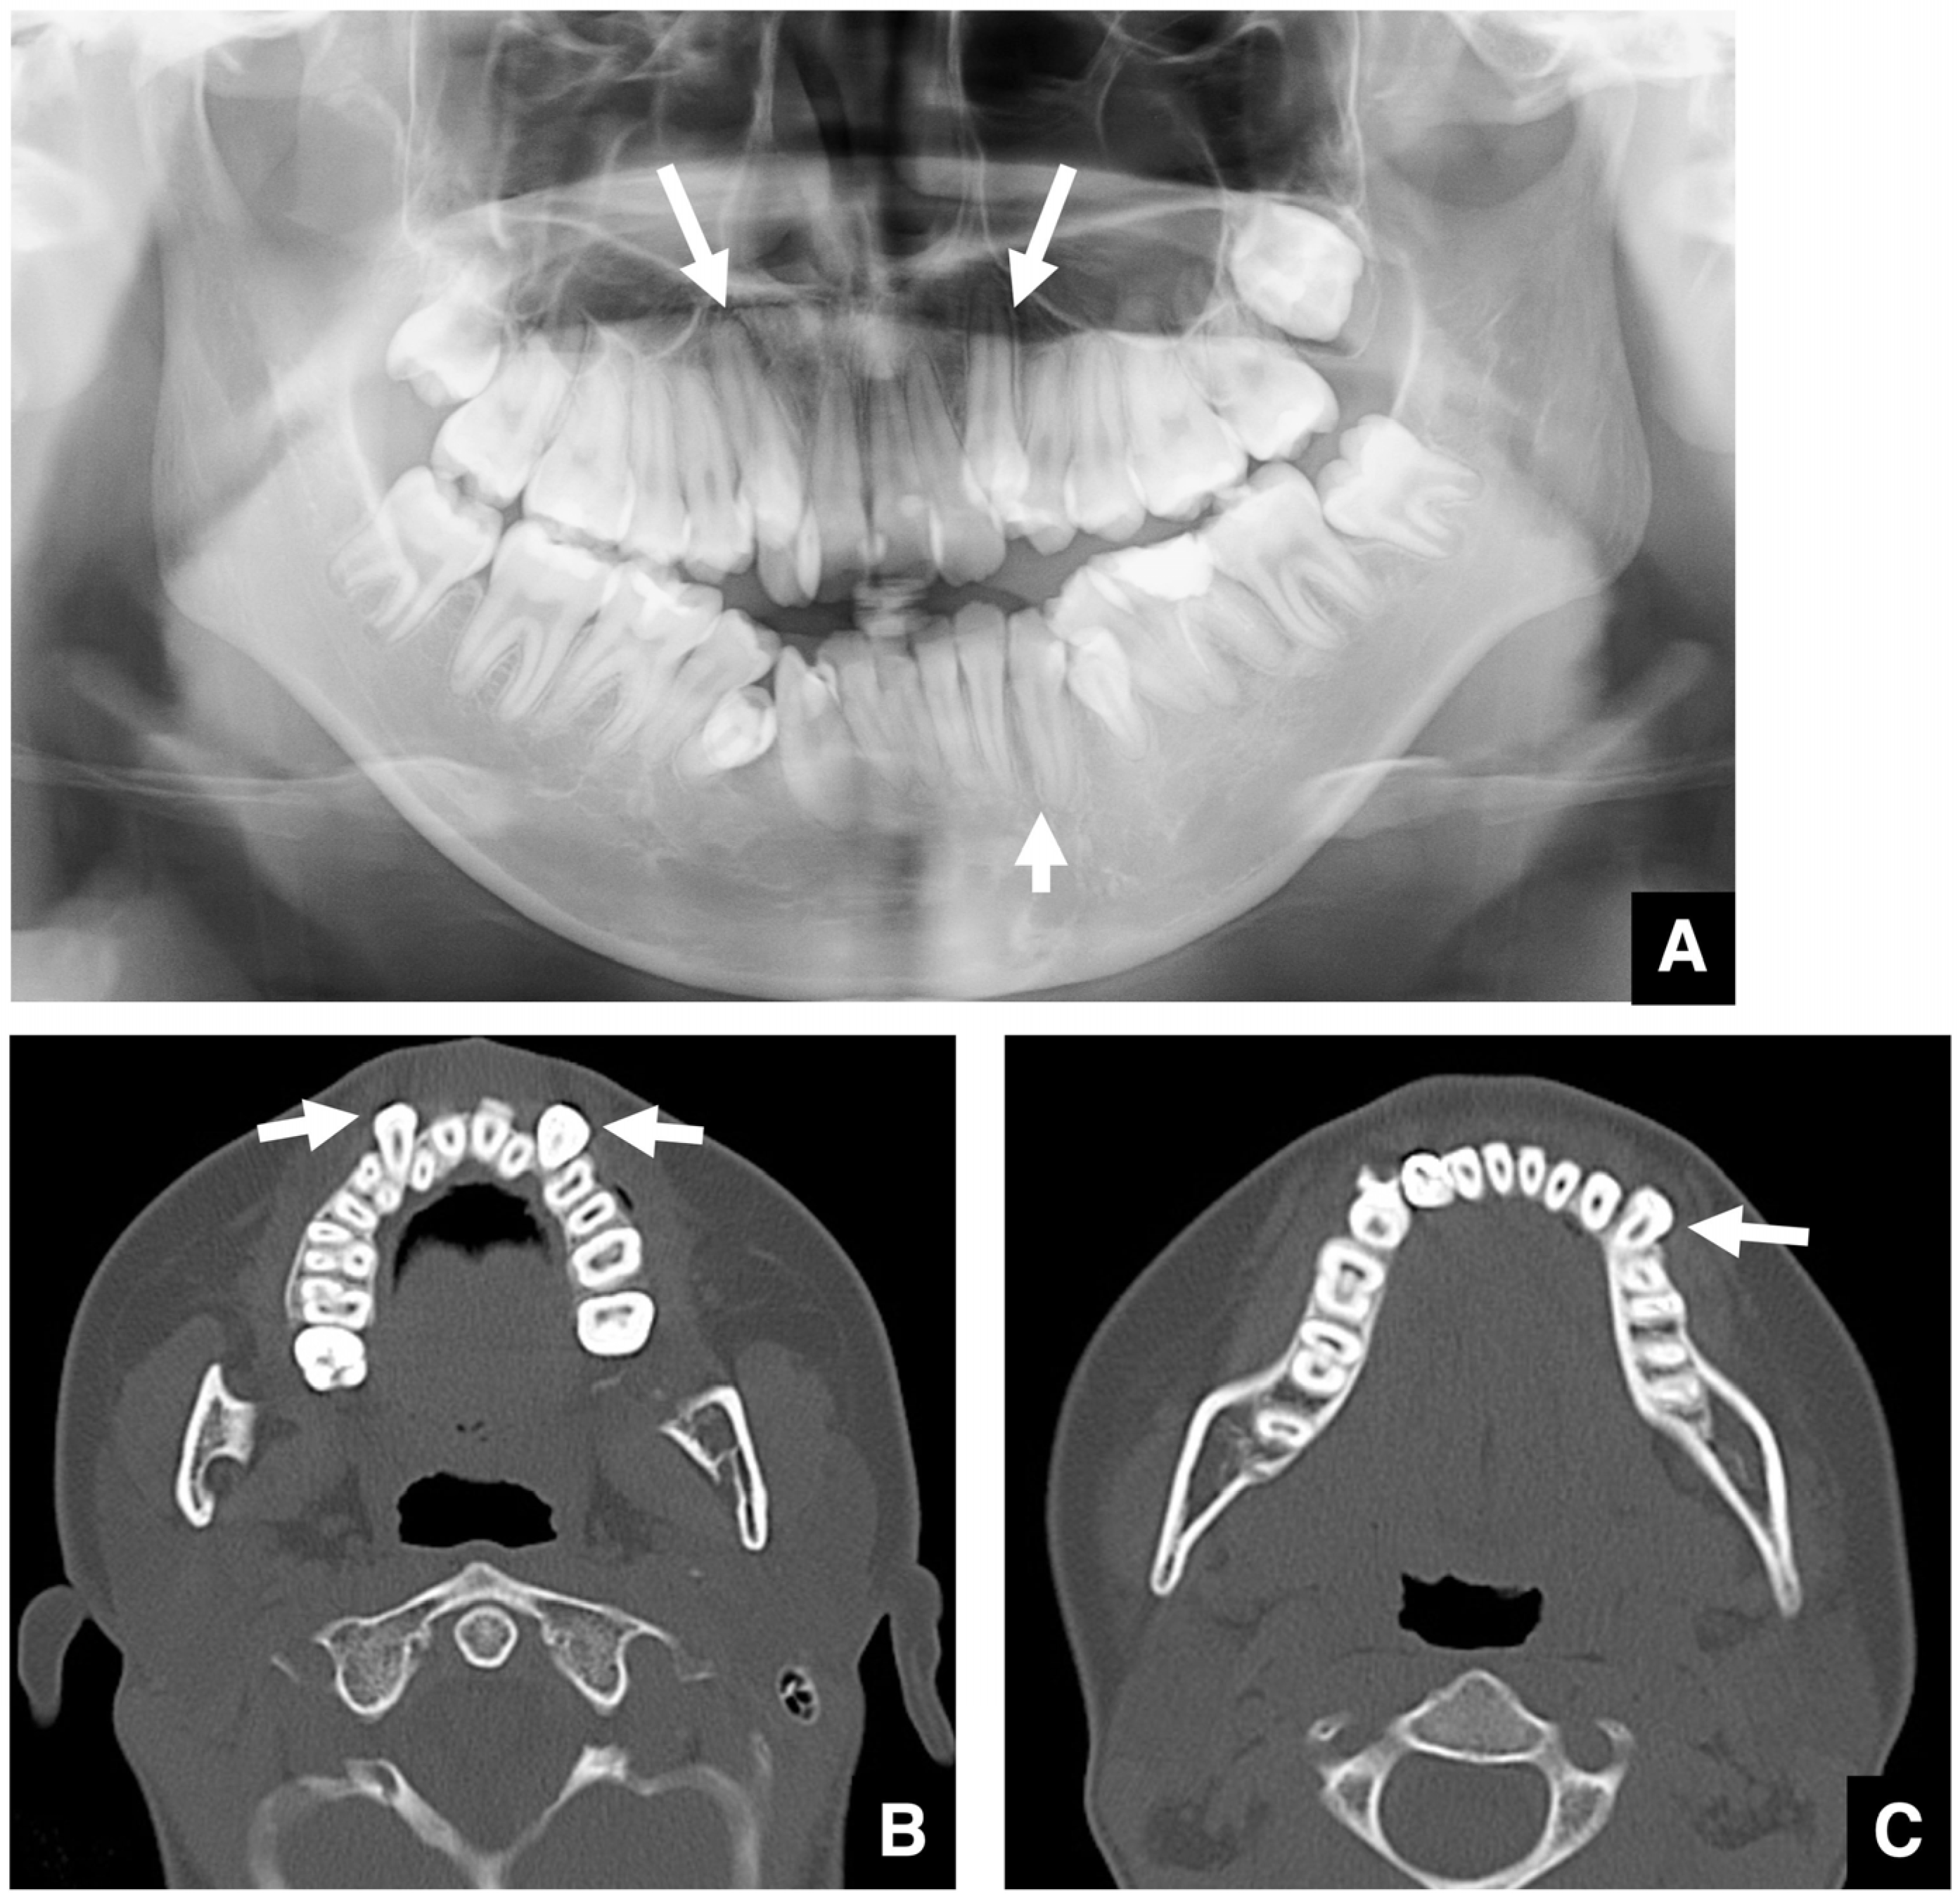

- Jung, Y.H.; Liang, H.; Benson, B.W.; Flint, D.J.; Cho, B.H. The assessment of impacted maxillary canine position with panoramic radiography and cone beam CT. Dentomaxillofac. Radiol. 2012, 41, 356–360. [Google Scholar] [CrossRef]

- Ghai, S.; Choudhury, S. Role of panoramic imaging and cone beam CT for assessment of inferior alveolar nerve exposure and subsequent paresthesia following removal of impacted mandibular third molar. J. Oral Maxillofac. Surg. 2018, 17, 242–247. [Google Scholar] [CrossRef]